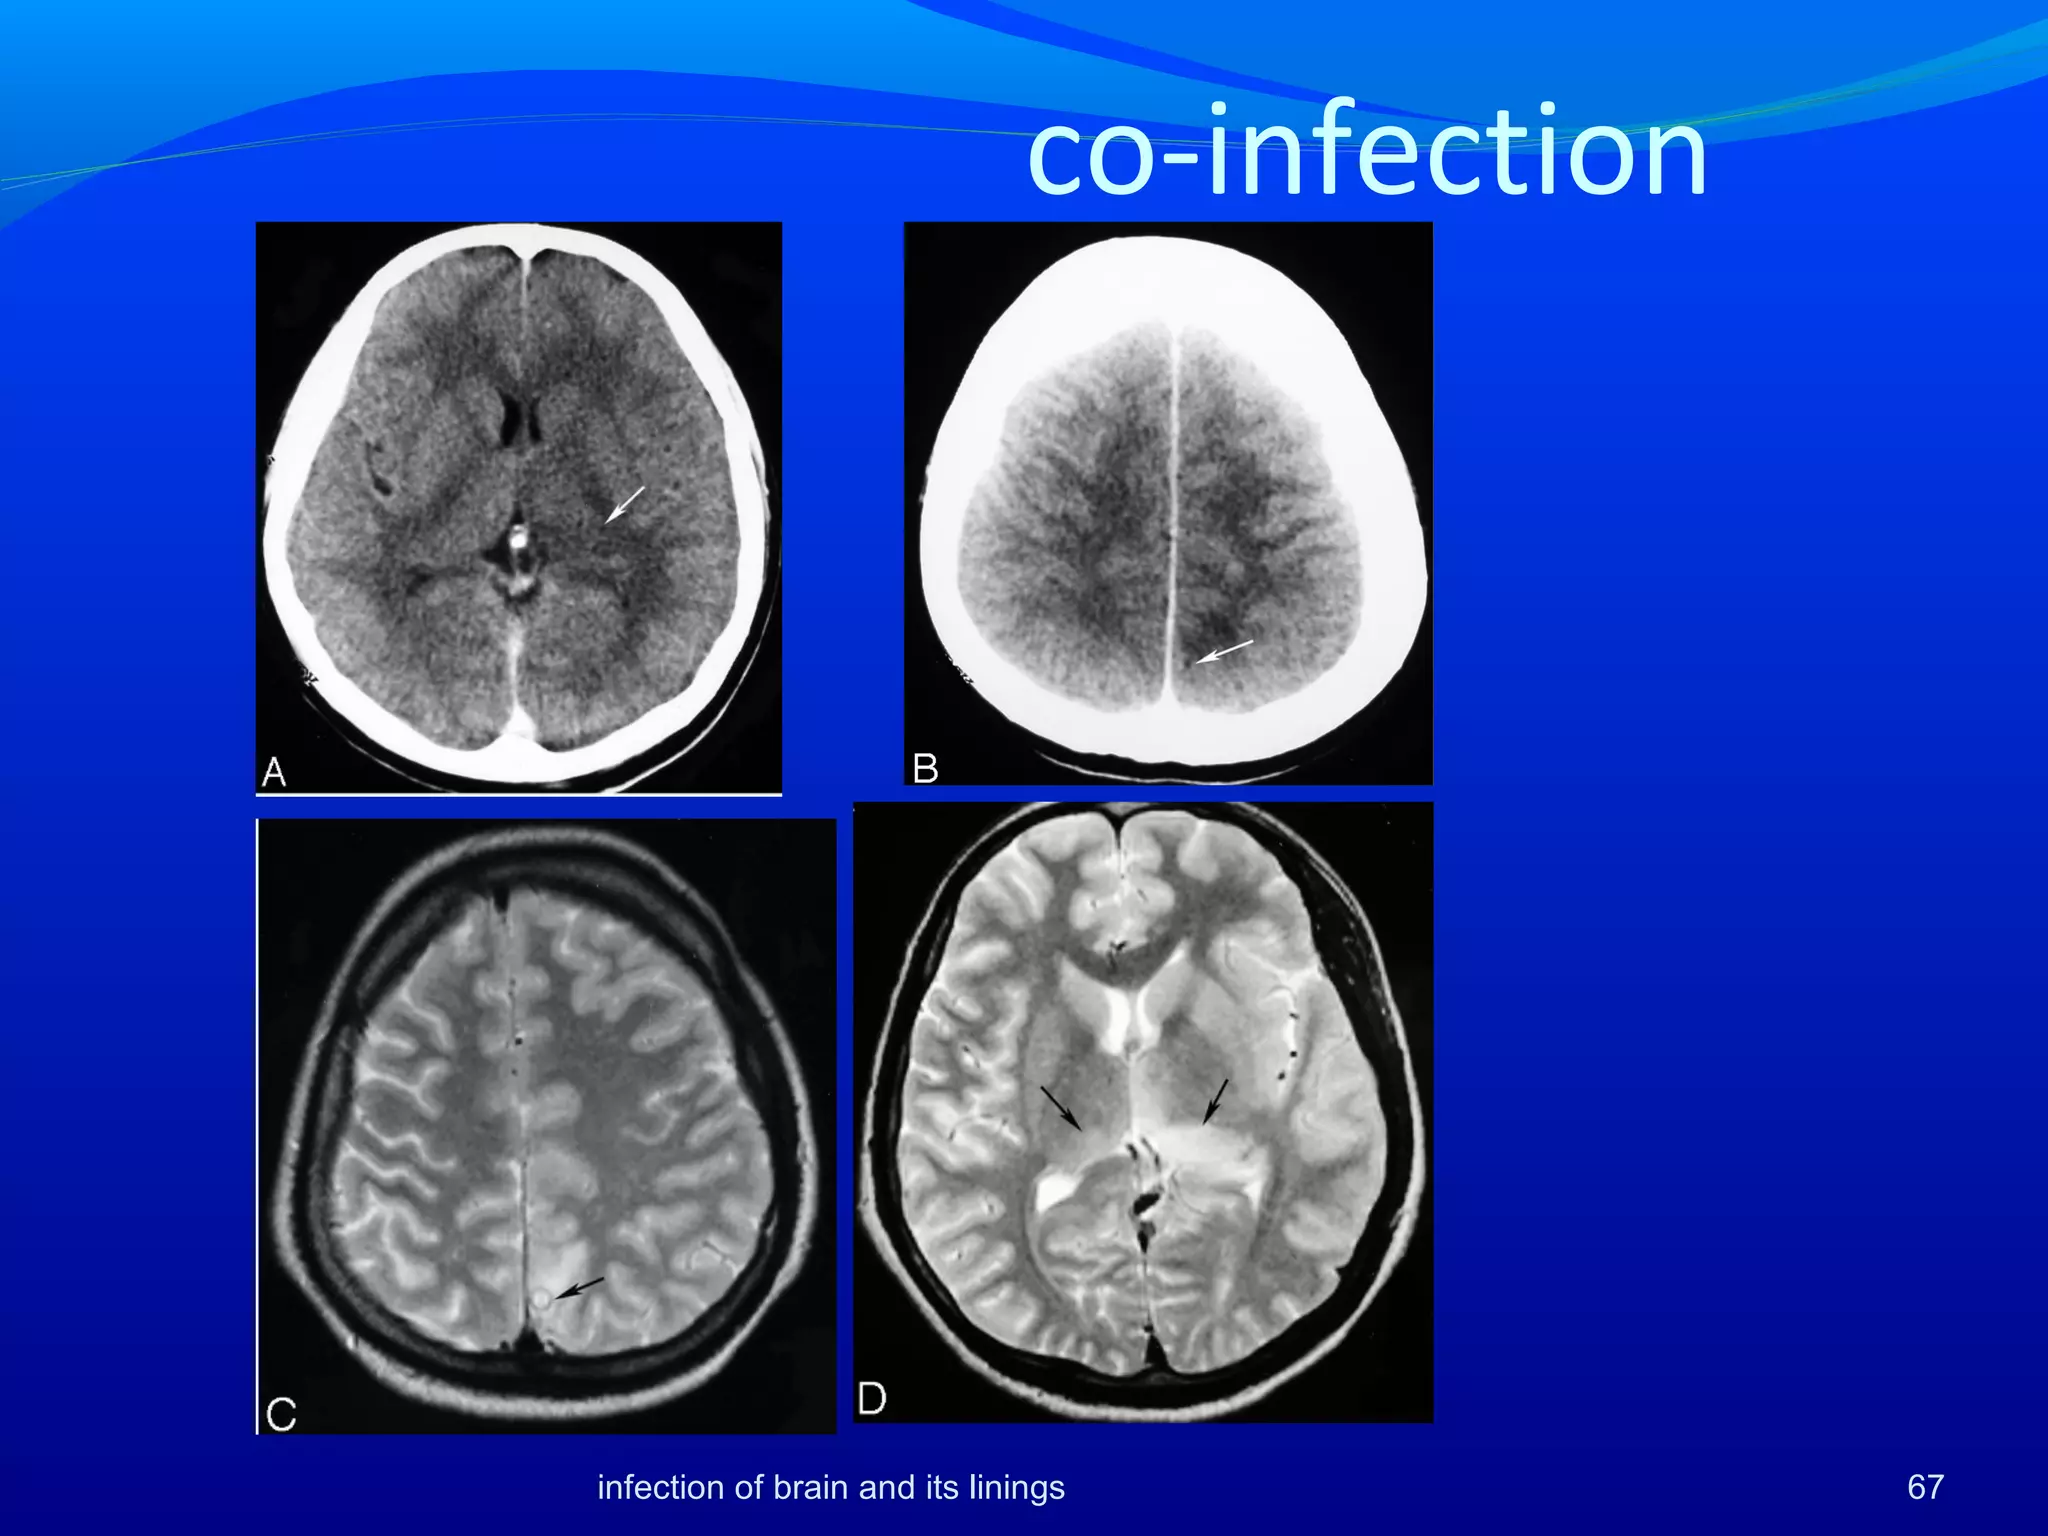

Neurocysticercosis and JE Morethan a casual relationship between NCC and JE has been suggested by many studies in China and India [1,2,3] Co-infections have been advocated as prognosticator of poor outcome[1] 1.Desai Epidemiol Infect 1997;118:165 2. Shankar. Ind J Med Res 1983; 78:431 3. Liu. Chinese Med J 1957;75:1010 65infection of brain and its linings

• 66.

Neurocysticercosis and JE asymmetricwith lateralization to the side of the brain having maximum NCC or a cyst with edema. were more florid with significantly higher amount of abnormal CT scans and more abnormal MR imaging more common in children. Altered immune status in co-infections were suggested by significantly lowered levels of JE IgM. 66infection of brain and its linings

• 67.

infection of brainand its linings 67 co-infection